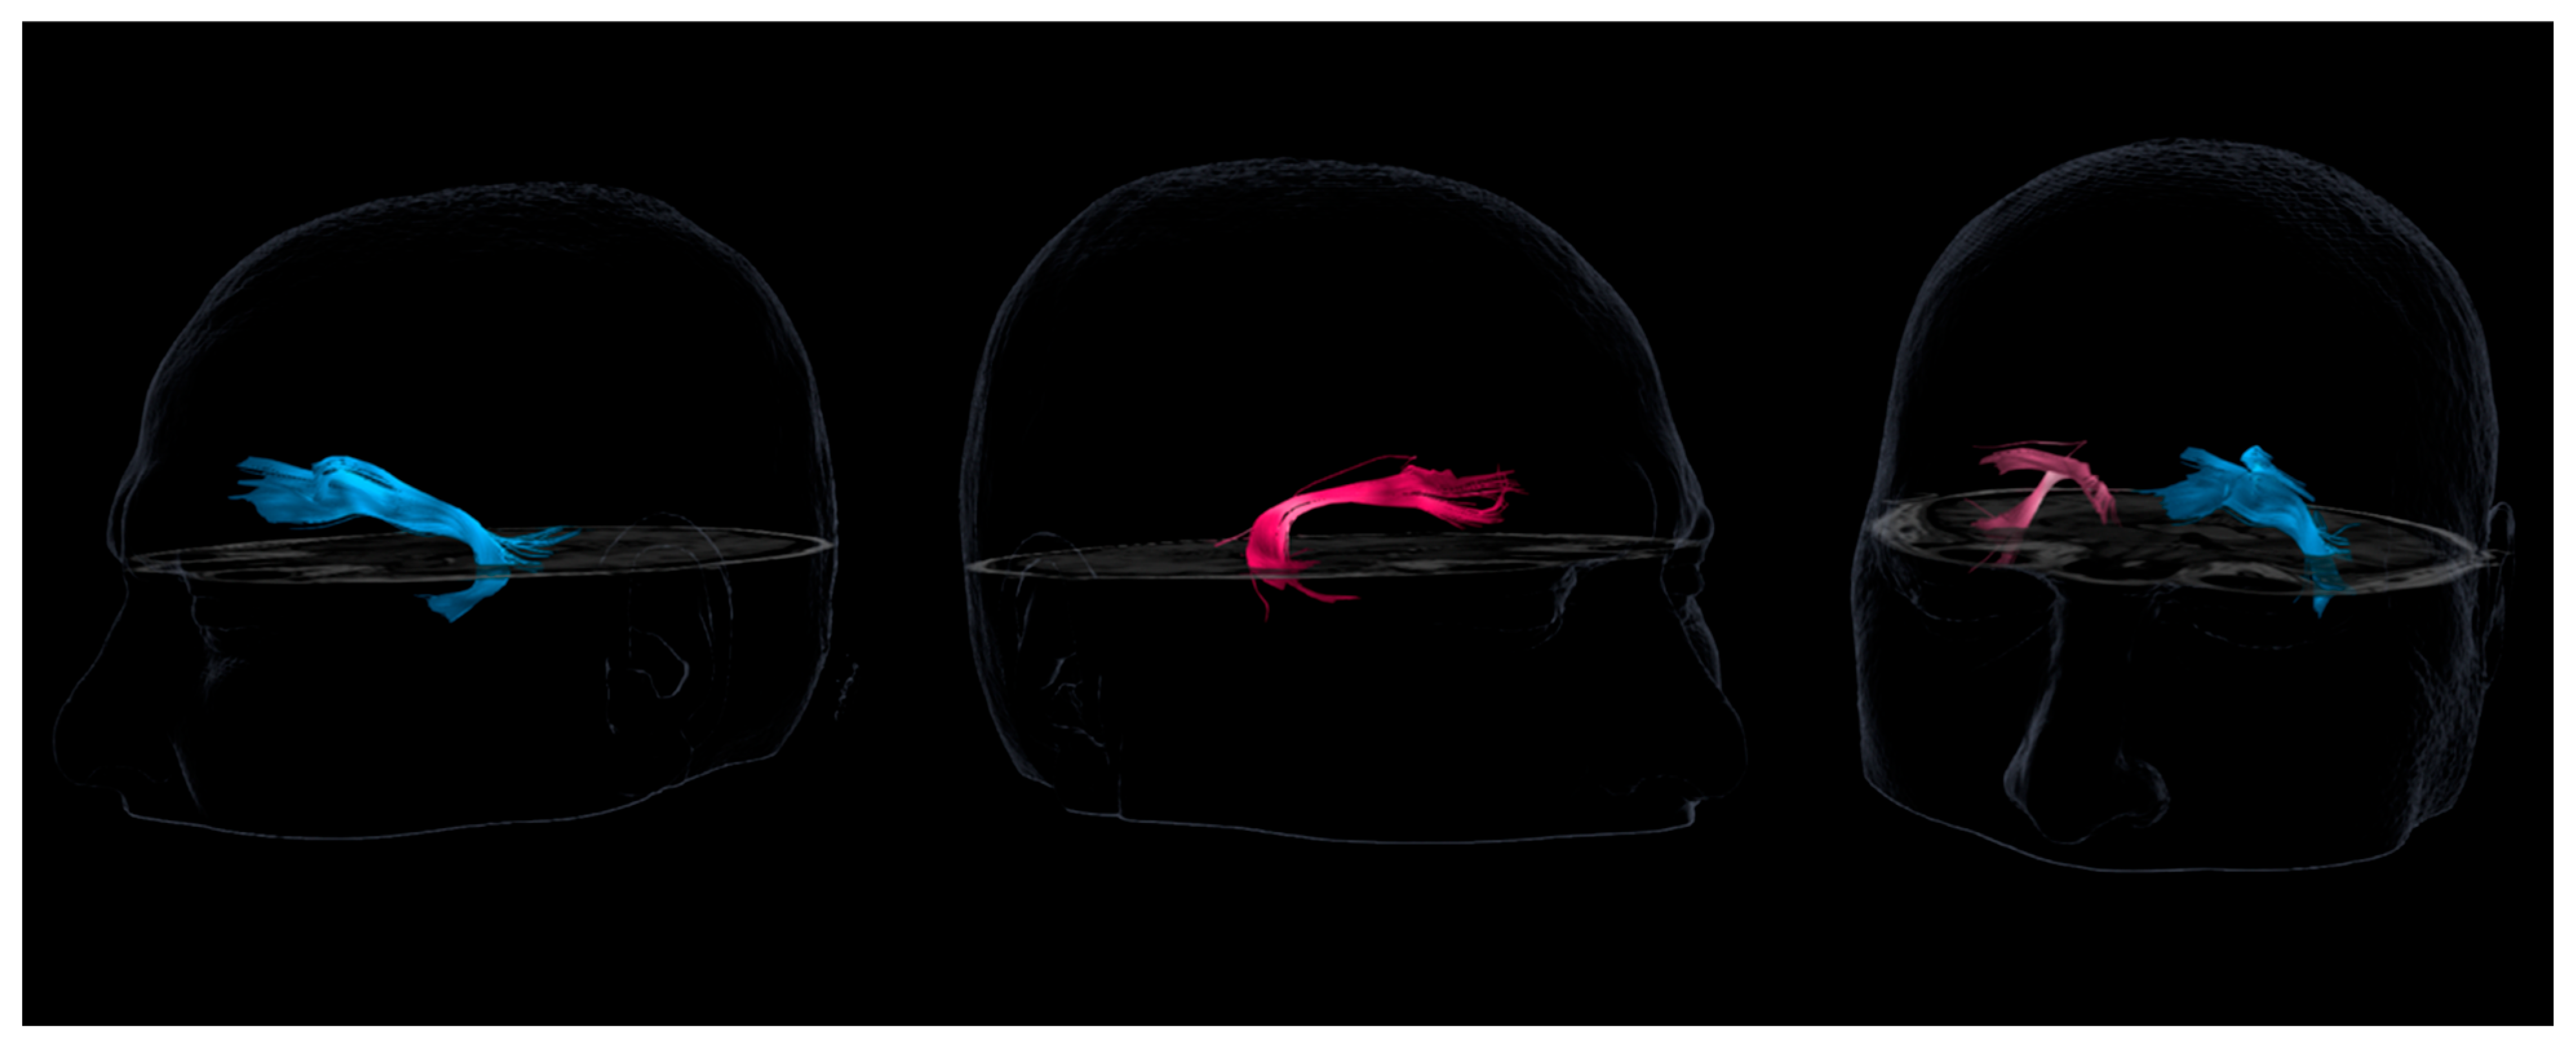

5.3.2. Diffusion Tensor Imaging (DTI) Tractography

- The correlation with alteration of the right uncinate fasciculus supports the hypothesis that this white matter tract may act as a key modulator in the propagation of epileptic activity toward frontal regions involved in meaning attribution.